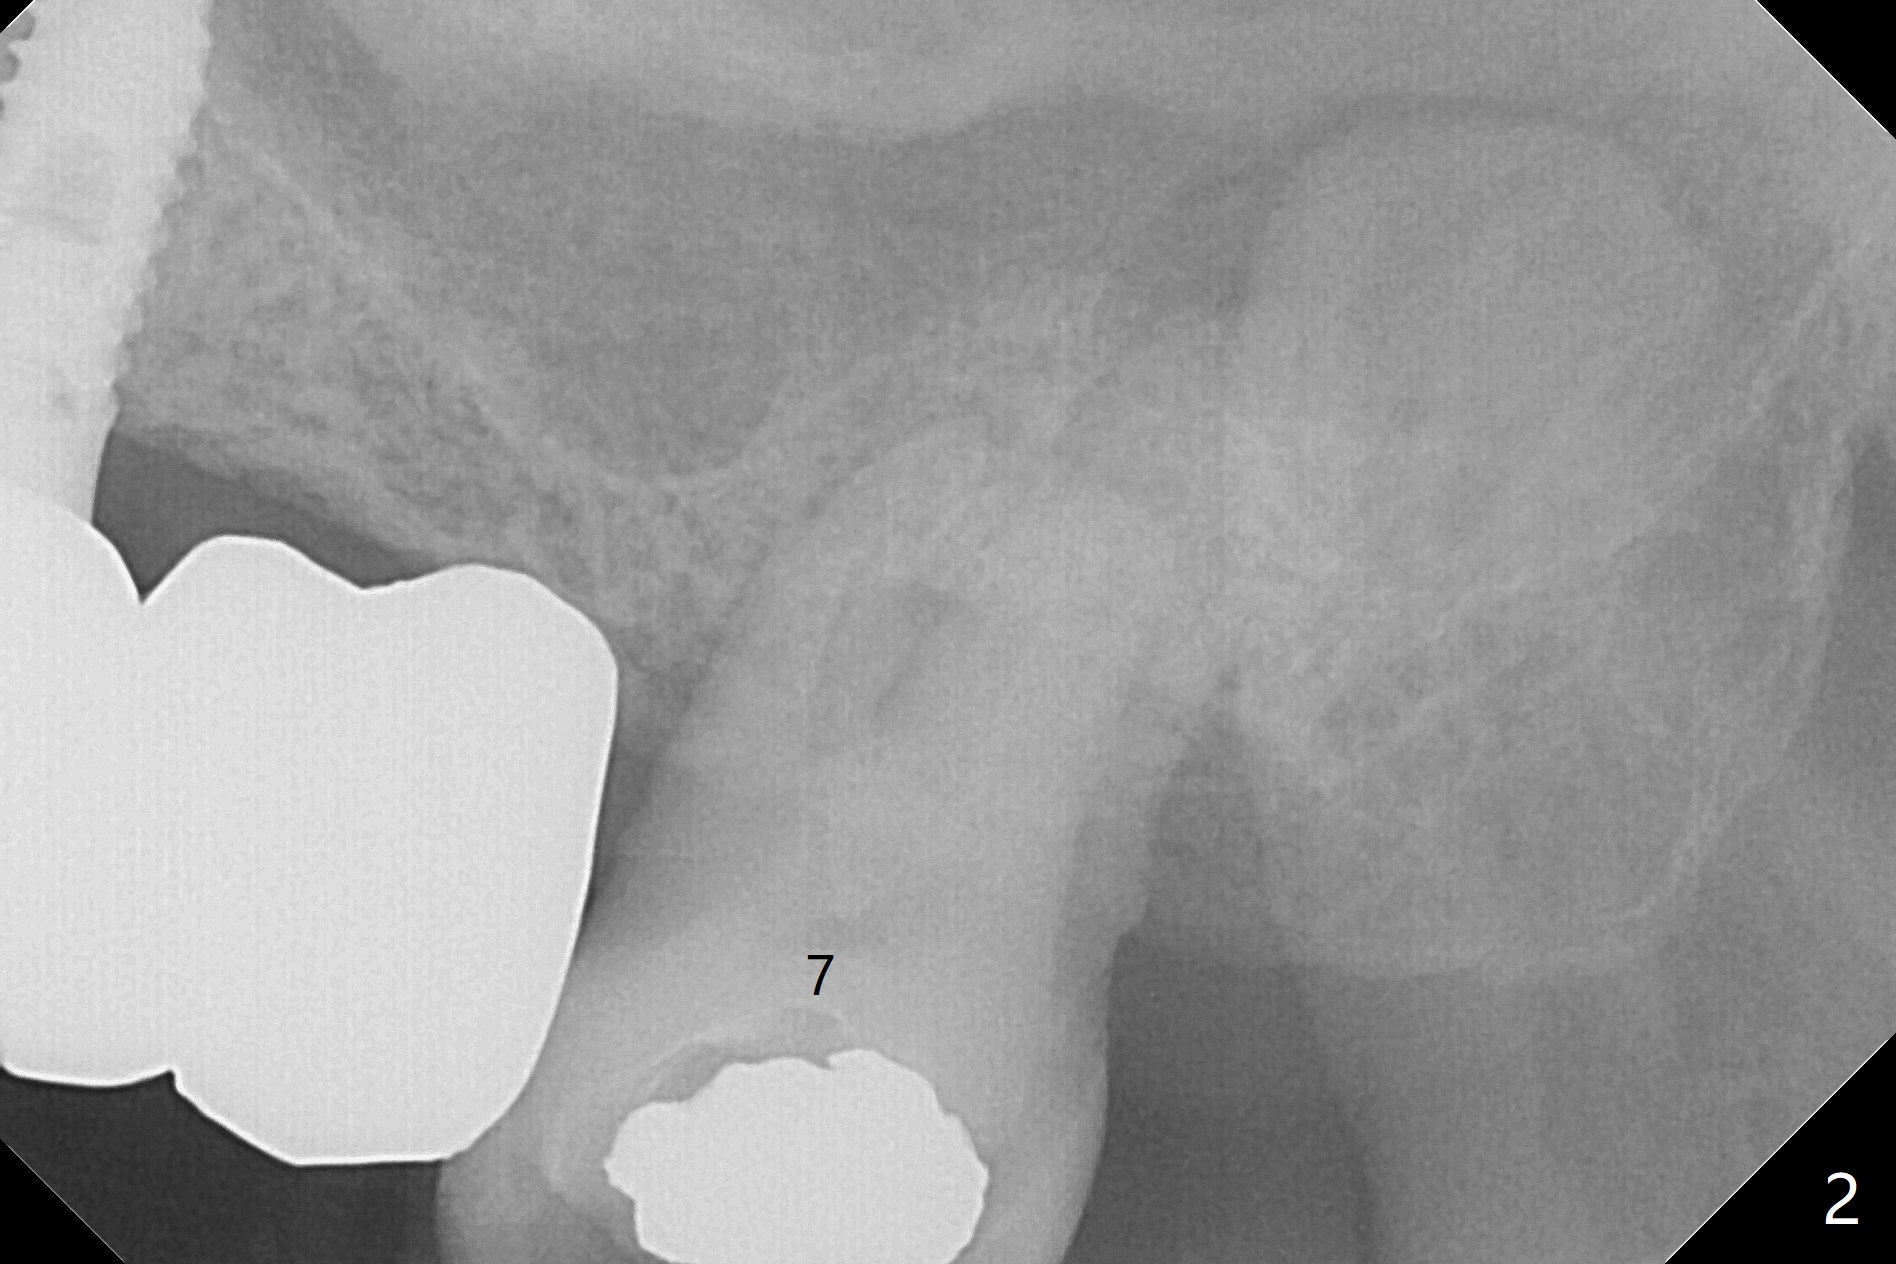

86岁男左上7折裂(图一),要求拔除,经过讨论(7拔除后,4-6悬臂桥可能断裂,对植体产生创伤,图二(左下7存在)),同意植骨。拔牙时发现中隔特别粗大(图三,五:S),三个牙槽窝根尖好像在中隔下面相互交通,擤鼻涕却没有气泡,仿佛与上颌窦没有相通。艰难清创后,放置Vanilla骨粉(图三),腭侧根特别容易填满,而颊侧根填入许多骨粉,术后CT远中颊侧骨粉尤其多(图四),上颌窦粘膜增厚(原来有季节性过敏)。术前根尖片显示远中颊侧根尖周围阴影很长(图五,六(虚线))。第二天早上鼻出血(仅有一次),今后牙槽窝明显比牙根长,清创控制深度,先放置胶原塞或PRF膜,后放骨粉。病人已经购买水牙线。术后7天树脂敷料稳定,局部卫生好(图七),骨粉好像进入上颌窦后部(图八)。术后1.5个月树脂敷料仍在原位,很容易撤除,牙槽窝愈合(图九),骨粉好像没有丢失(图十)。